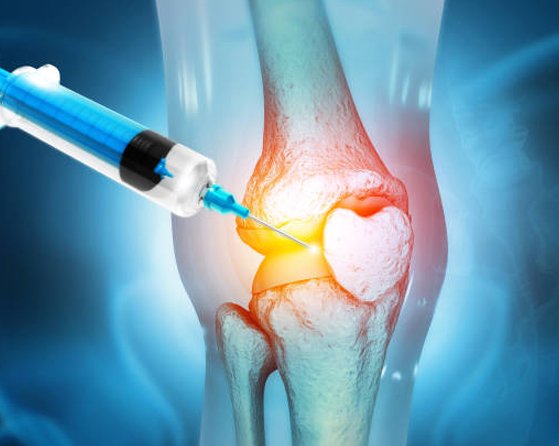

Platelet-Rich Plasma (PRP) Therapy : PRP involves injecting a concentrated solution of the patient\’s own platelets into the affected area. PRP promotes tissue healing and reduces inflammation, offering potential relief for conditions like meniscus tears and osteoarthritis.

Prolotherapy : This technique involves injecting a solution into the damaged or inflamed area to stimulate the body\’s natural healing response. Prolotherapy can target conditions such as ligament injuries and osteoarthritis.

Regenerative therapy for knee pain involves advanced, minimally invasive procedures designed to stimulate natural healing and repair of damaged tissues. Common techniques include Platelet-Rich Plasma (PRP) therapy and stem cell therapy, both of which promote tissue regeneration and reduce inflammation.